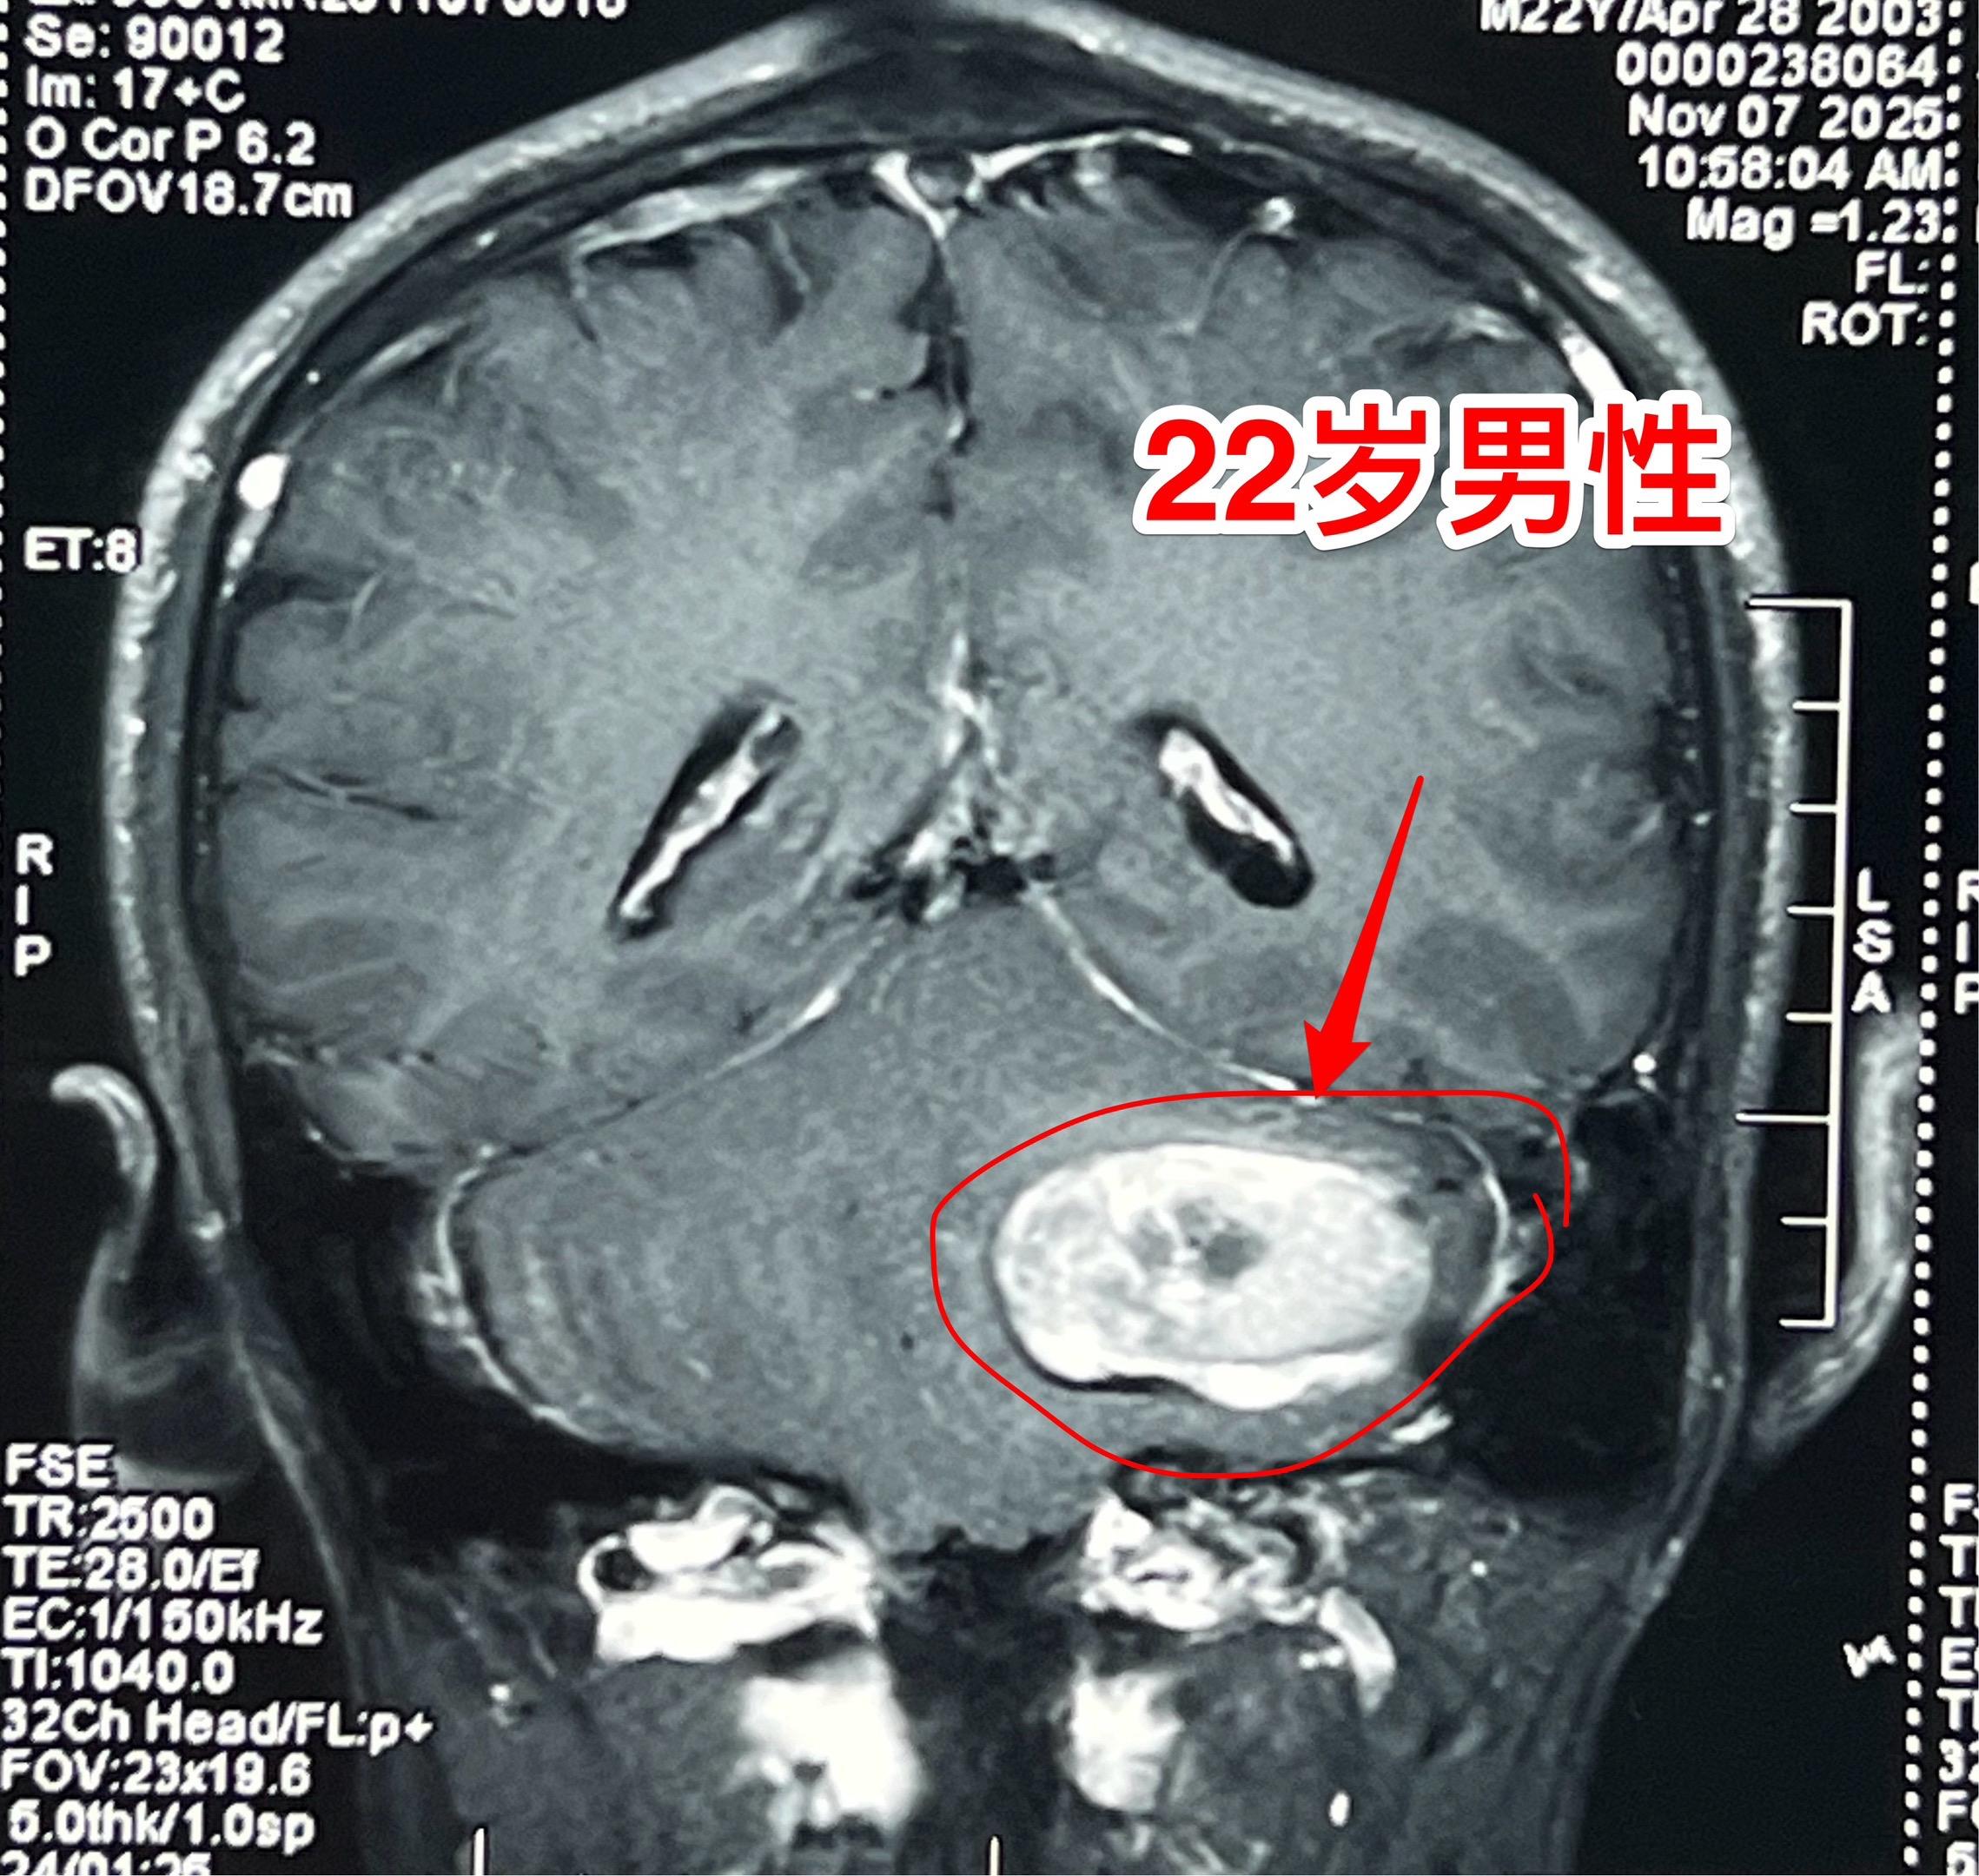

海绵状血管瘤出血。22岁辽宁省小伙子一周前突发头痛、乏力,一周之内几乎是昏昏沉沉、卧床不起。 CT和磁共振显示左侧小脑有陈旧出血。 11月16日作了手术,将病灶完全切除。术中显示病灶是海绵状血管瘤出血。 脑部海绵状血管瘤是先天性血管畸形的一种。如果出血了可能会造成头痛、癫痫发作、偏瘫等症状,需要作手术切除。如果不出血则对病人不造成危害,就不用作手术切除。海绵状血管瘤